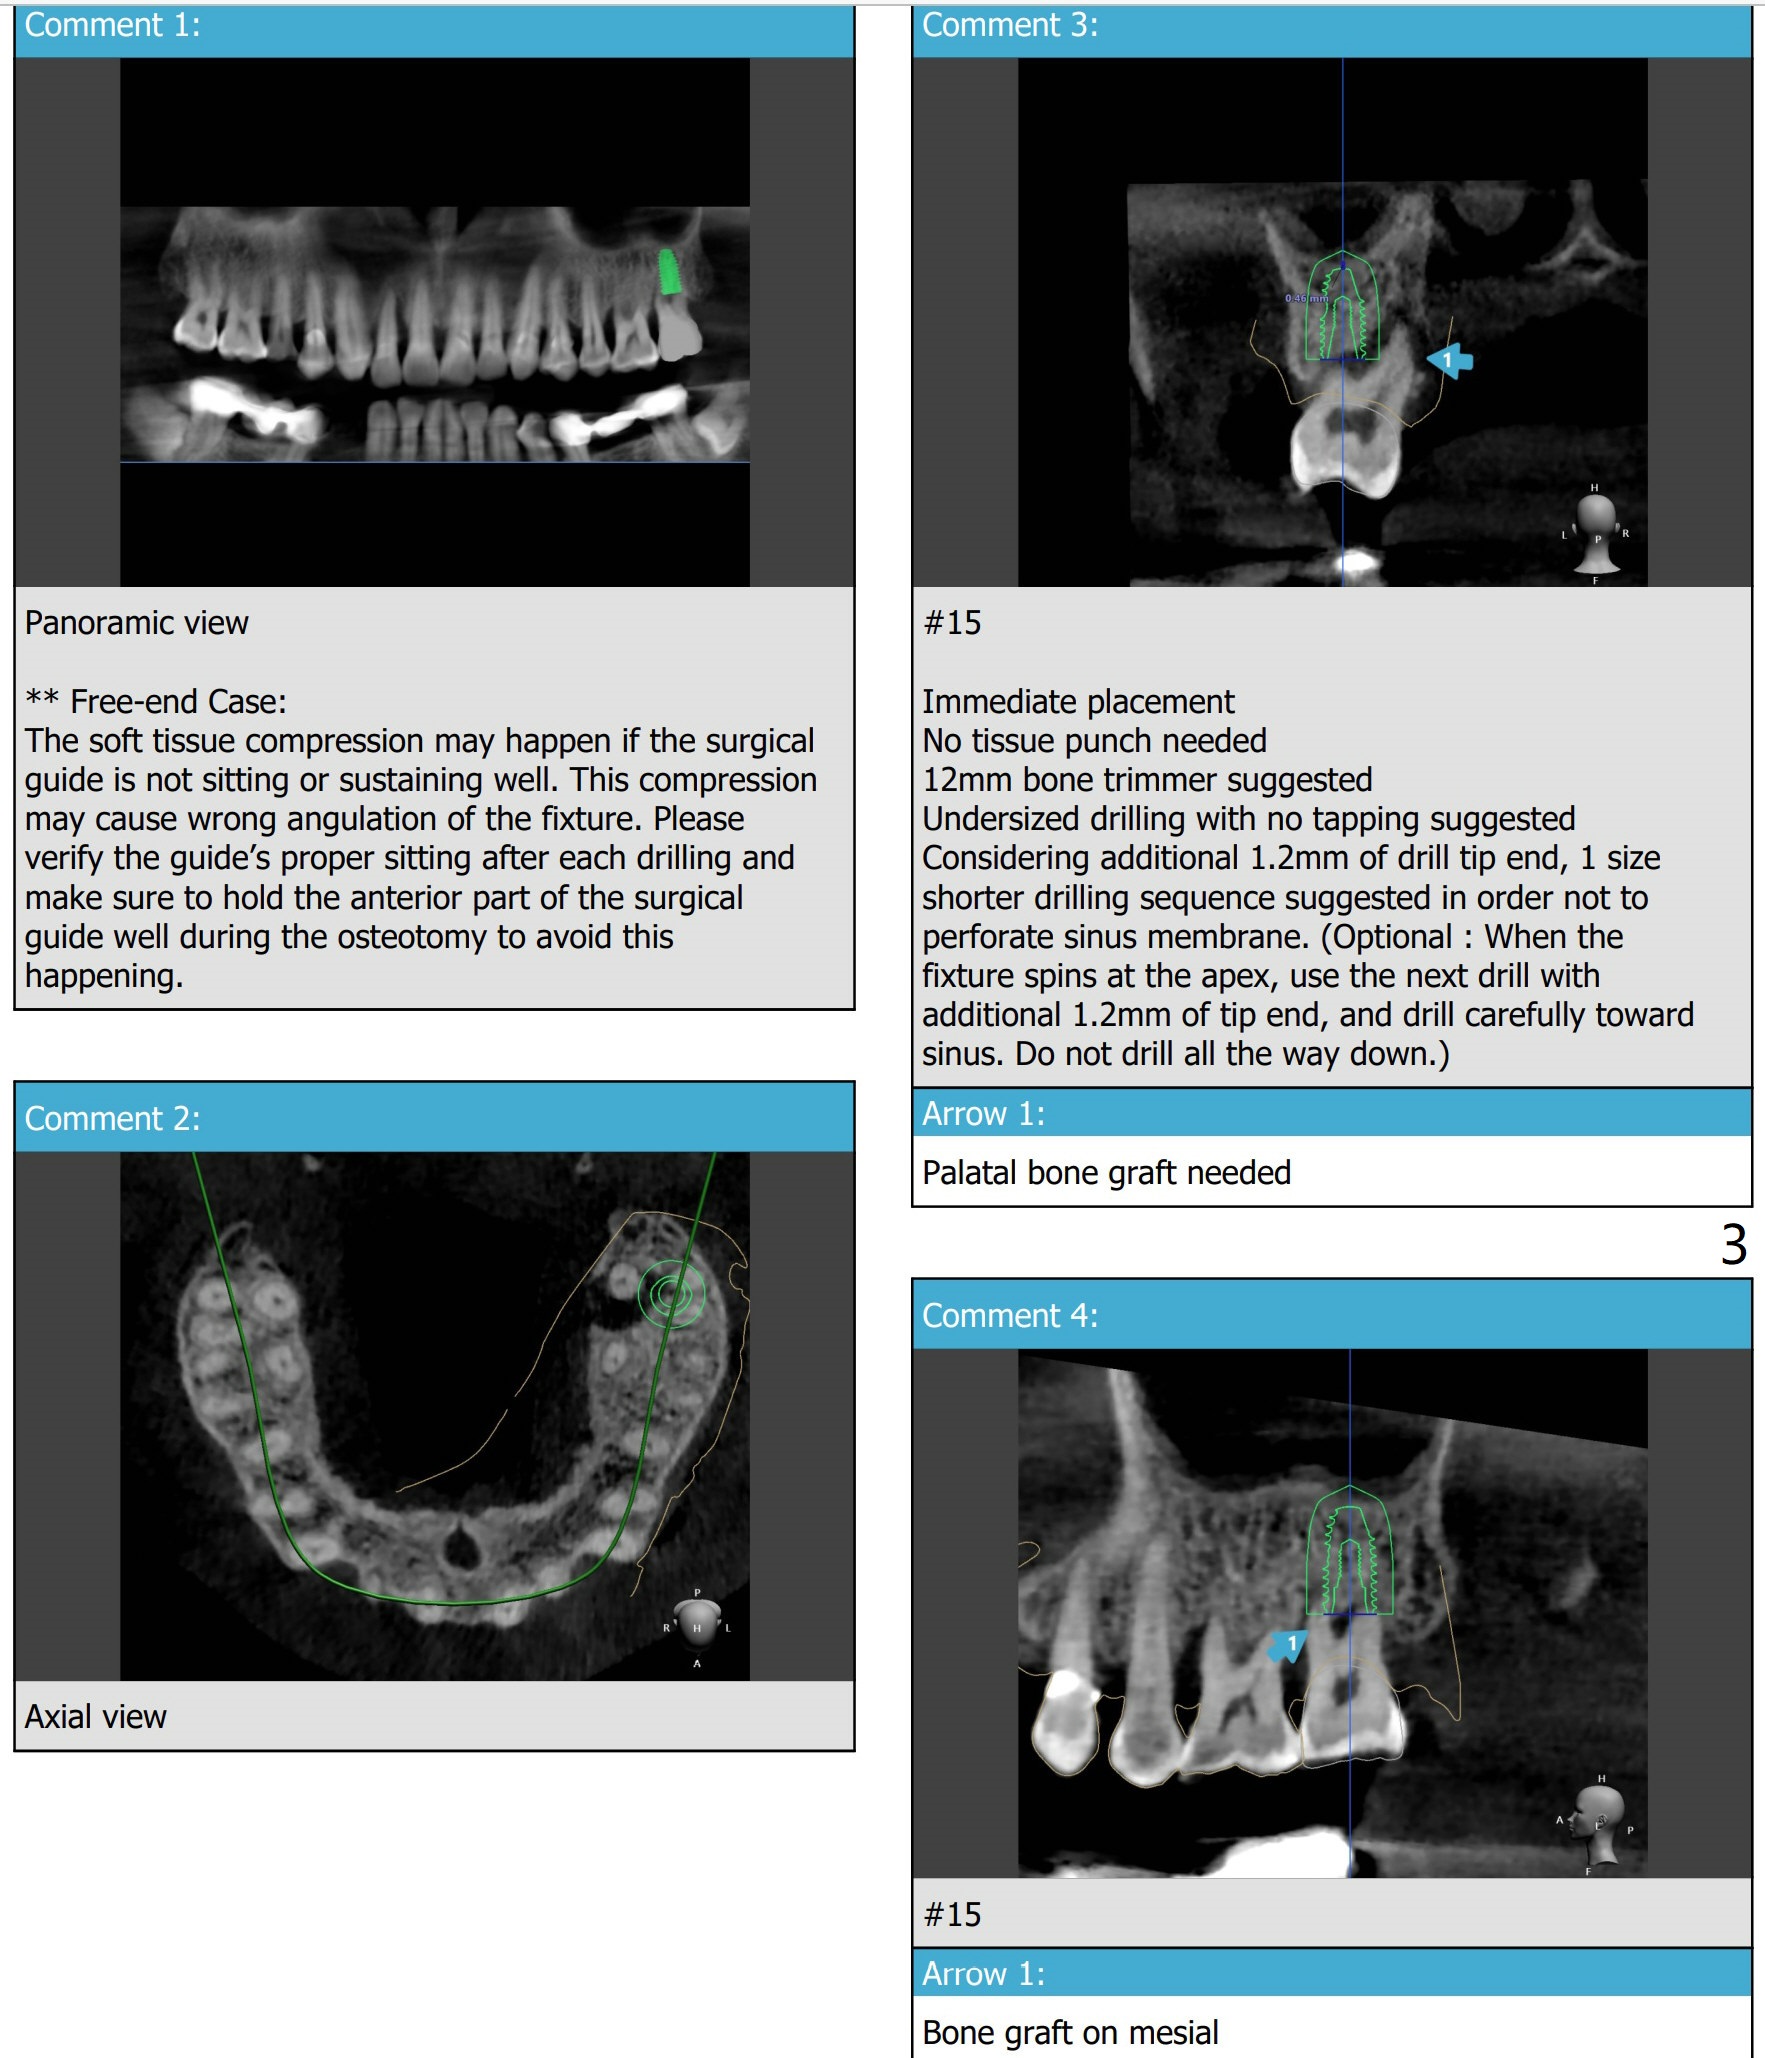

Guide Makes Implant Placement Safe

A 62-year-old man

Return to Protect Graft Oral Scanner

Xin Wei, DDS, PhD, MS 1st edition 06/18/2021, last revision 07/15/2021